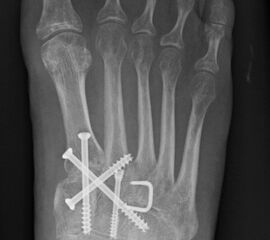

Bei frischen Verletzungen gelingt meist die geschlossene Reposition durch eine Repositionszange unter Bildverstärkerkontrolle. Anschließend wird über eine kleine mediale Inzision ein Kirschnerdraht vom Os cuneiforme mediale in die Metatarsale II-Basis gebohrt und das Lisfranc-Ligament durch eine Stellschraube in anatomischer Stellung ruhiggestellt. Durch weitere Schrauben lässt sich bei Bedarf das Tarsometatarsale I-Gelenk und der Raum zwischen Os cuneiforme I und II stabilisieren. Nach Lagekontrolle unter dem Bildverstärker wird eine durchbohrte Schraube mit durchgehendem Gewinde eingebracht (Abb. 14). Von der Verwendung von Zugschrauben wird abgeraten, da diese eine unnötige und unphysiologische Kompression der Gelenkflächen erzeugen.

Zum Lesen der Bildbeschreibung und zur Vollansicht bitte das Bild anklicken.

In der Regel werden die physiologisch rigiden TMT-1 bis 3 mittels Schrauben transfixiert. Hierfür werden meist kanülierte Kleinfragment-Kortikalisschrauben (3,5 oder 4 mm) verwendet. Diese können in Stellschraubentechnik von der Metatarsale-1-Basis in das Os cuneiforme mediale (Abb. 17) sowie vom Os cuneifome mediale in die Metatarsale-2-Basis und bei zusätzlicher intercuneiformer Instabilität vom Os cuneifome mediale in das Os cuneifome intermedium eingebracht werden.